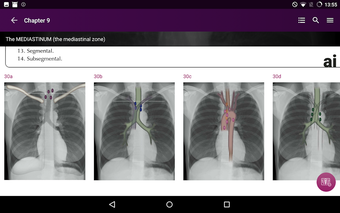

Radioloji'yi Keşfet: Göğüs Röntgeni Yorumlama, göğüs röntgeninin yorumlanmasının anlaşılmasını artırmak için tasarlanmış bir eğitim uygulamasıdır ve doktorlar, tıp öğrencileri ve radyologlar tarafından kullanılması amaçlanmaktadır. Uygulama, en küçük detayları görüntülemek için yakınlaştırılabilecek yüksek kaliteli görüntüler ve her bulgunun önemini anlamanıza yardımcı olacak bir sesli yorum içerir.

Uygulamanın amacı, kullanıcıların farklı x-ışını bulgularını ve bunların bir hastalığın teşhisinde nasıl kullanılabileceğini daha iyi anlamalarına yardımcı olmaktır. Uygulama, göğüs röntgeni yorumlaması için gerekli çeşitli yapı taşlarını kapsayan 5 bölüme ayrılmıştır.